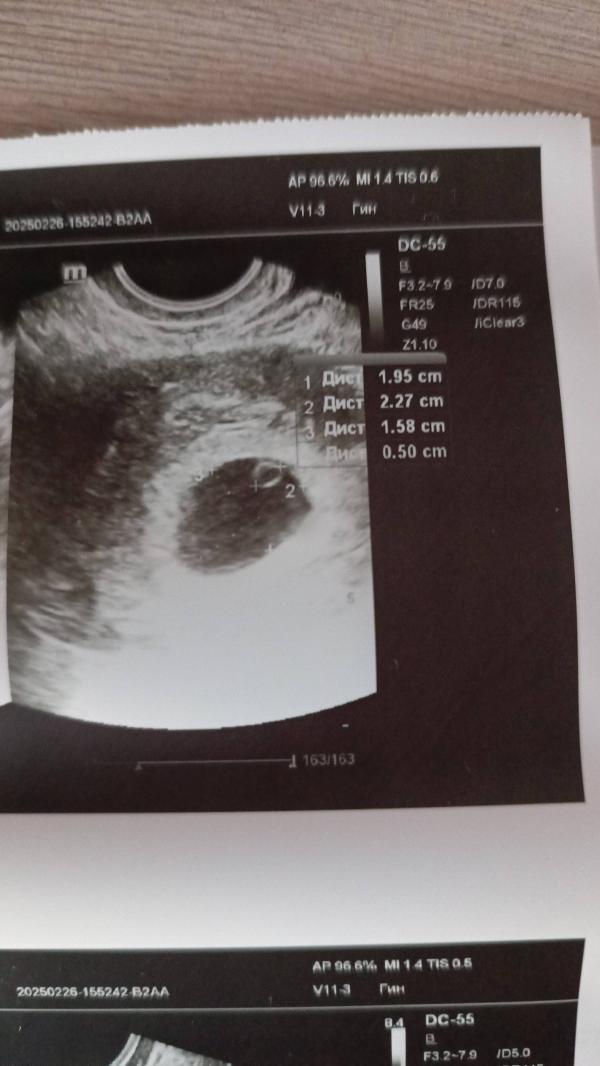

Срок по заключению 8 недель, значит либо эмбриона видно должно быть, либо он не стал смотреть, как сказал видно что колышется только. Либо беременность не развивается 🤷 либо непонятно как он установил срок. Хотя желточный мешочек судя по таблицам 5мм соответствует сроку 8-9 недель... На таком сроке уже узи должно быть достаточно мне кажется без хгч в динамике 🤷♀️

Он просто говорил мне что срок очень маленький не видно ничего, а в заключении написал 8 недель, что непонятно 🤷

В 8 недель уже хороший эмбрион должен быть . а то срок ставит не пойми по каким параметрам

Я так поняла по желточному мешичку... И не понятно развивается ли беременность или нет...

@1832 по жм. Срок не ставят. Ставят по размеру плодного яйца если нет эмбриона. Если эмбрион появился то по ктр эмбриона. У вас вообще странное заключение.

Как понимаю на снимке жм, а эмбриона и не видать , в описании тоже нет , попробуйте завтра сходить в другое место